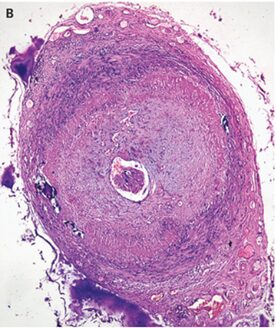

巨細胞性動脈炎の一例:側頭動脈肥厚著明例です。

側頭動脈エコーでは血管内腔の周囲の低エコー領域である「ハローサイン」を伴うびまん性の壁肥厚が明らかになった。側頭動脈生検が施行され、リンパ組織浸潤および高く巨細胞による動脈壁の壁肥厚が著明であった。